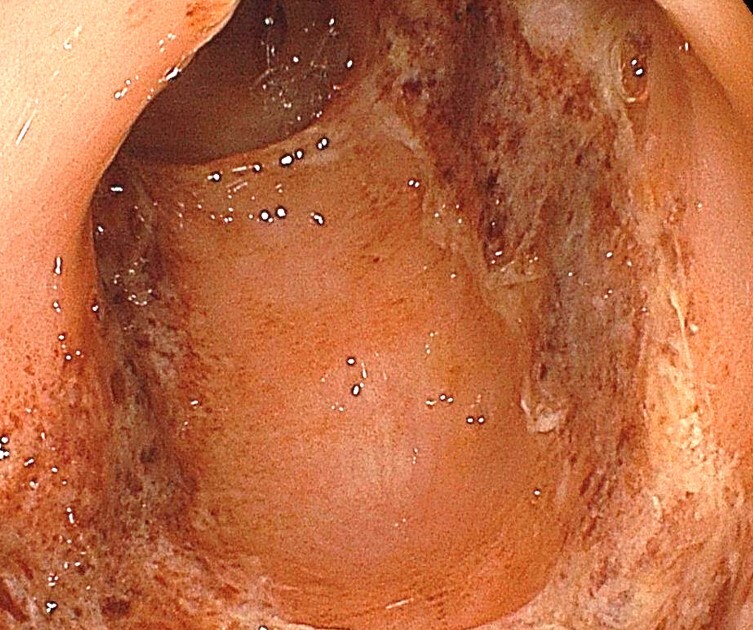

ピロリ菌陽性胃炎、粘膜の全体的な発赤や萎縮により血管が観察される

ピロリ陽性胃炎、同様に発赤と粘膜付着が強い